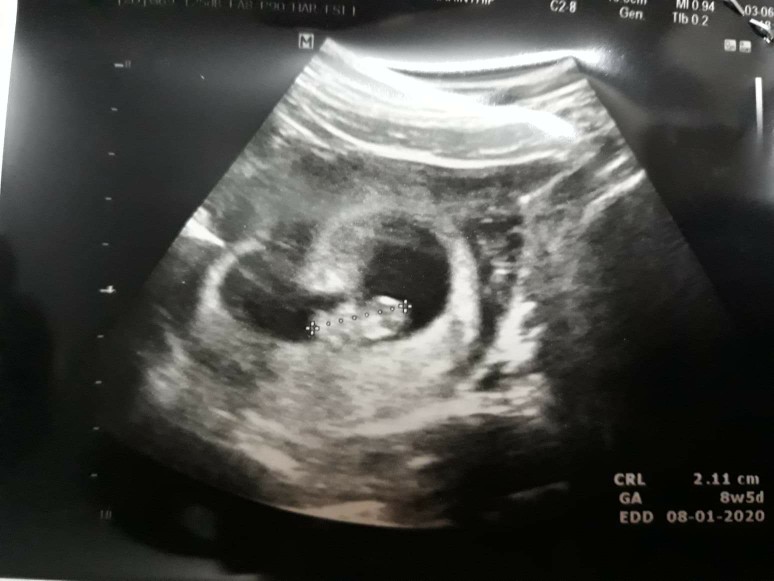

เจอตอน8weekชัดเลยสงสัยจะตัวใหญ๋ #เด็กยักษ์ของแม่😂